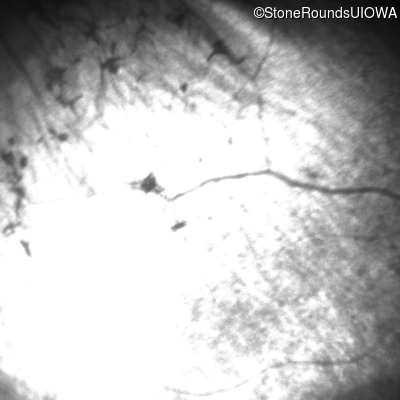

Infrared Fundus Photograph - Right - Light Perception

Exemplar